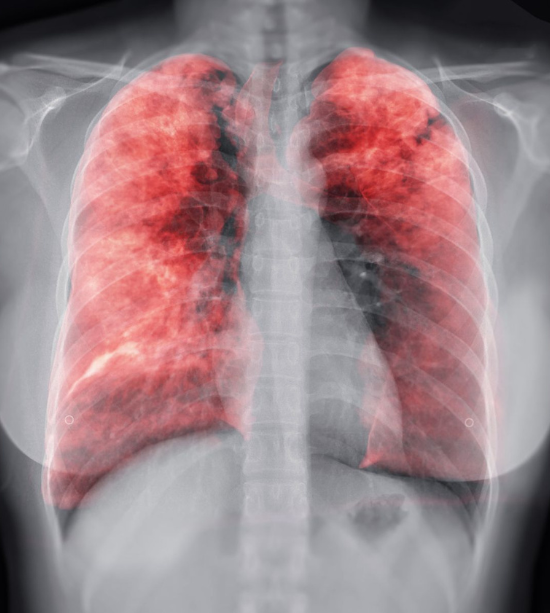

Advanced imaging techniques